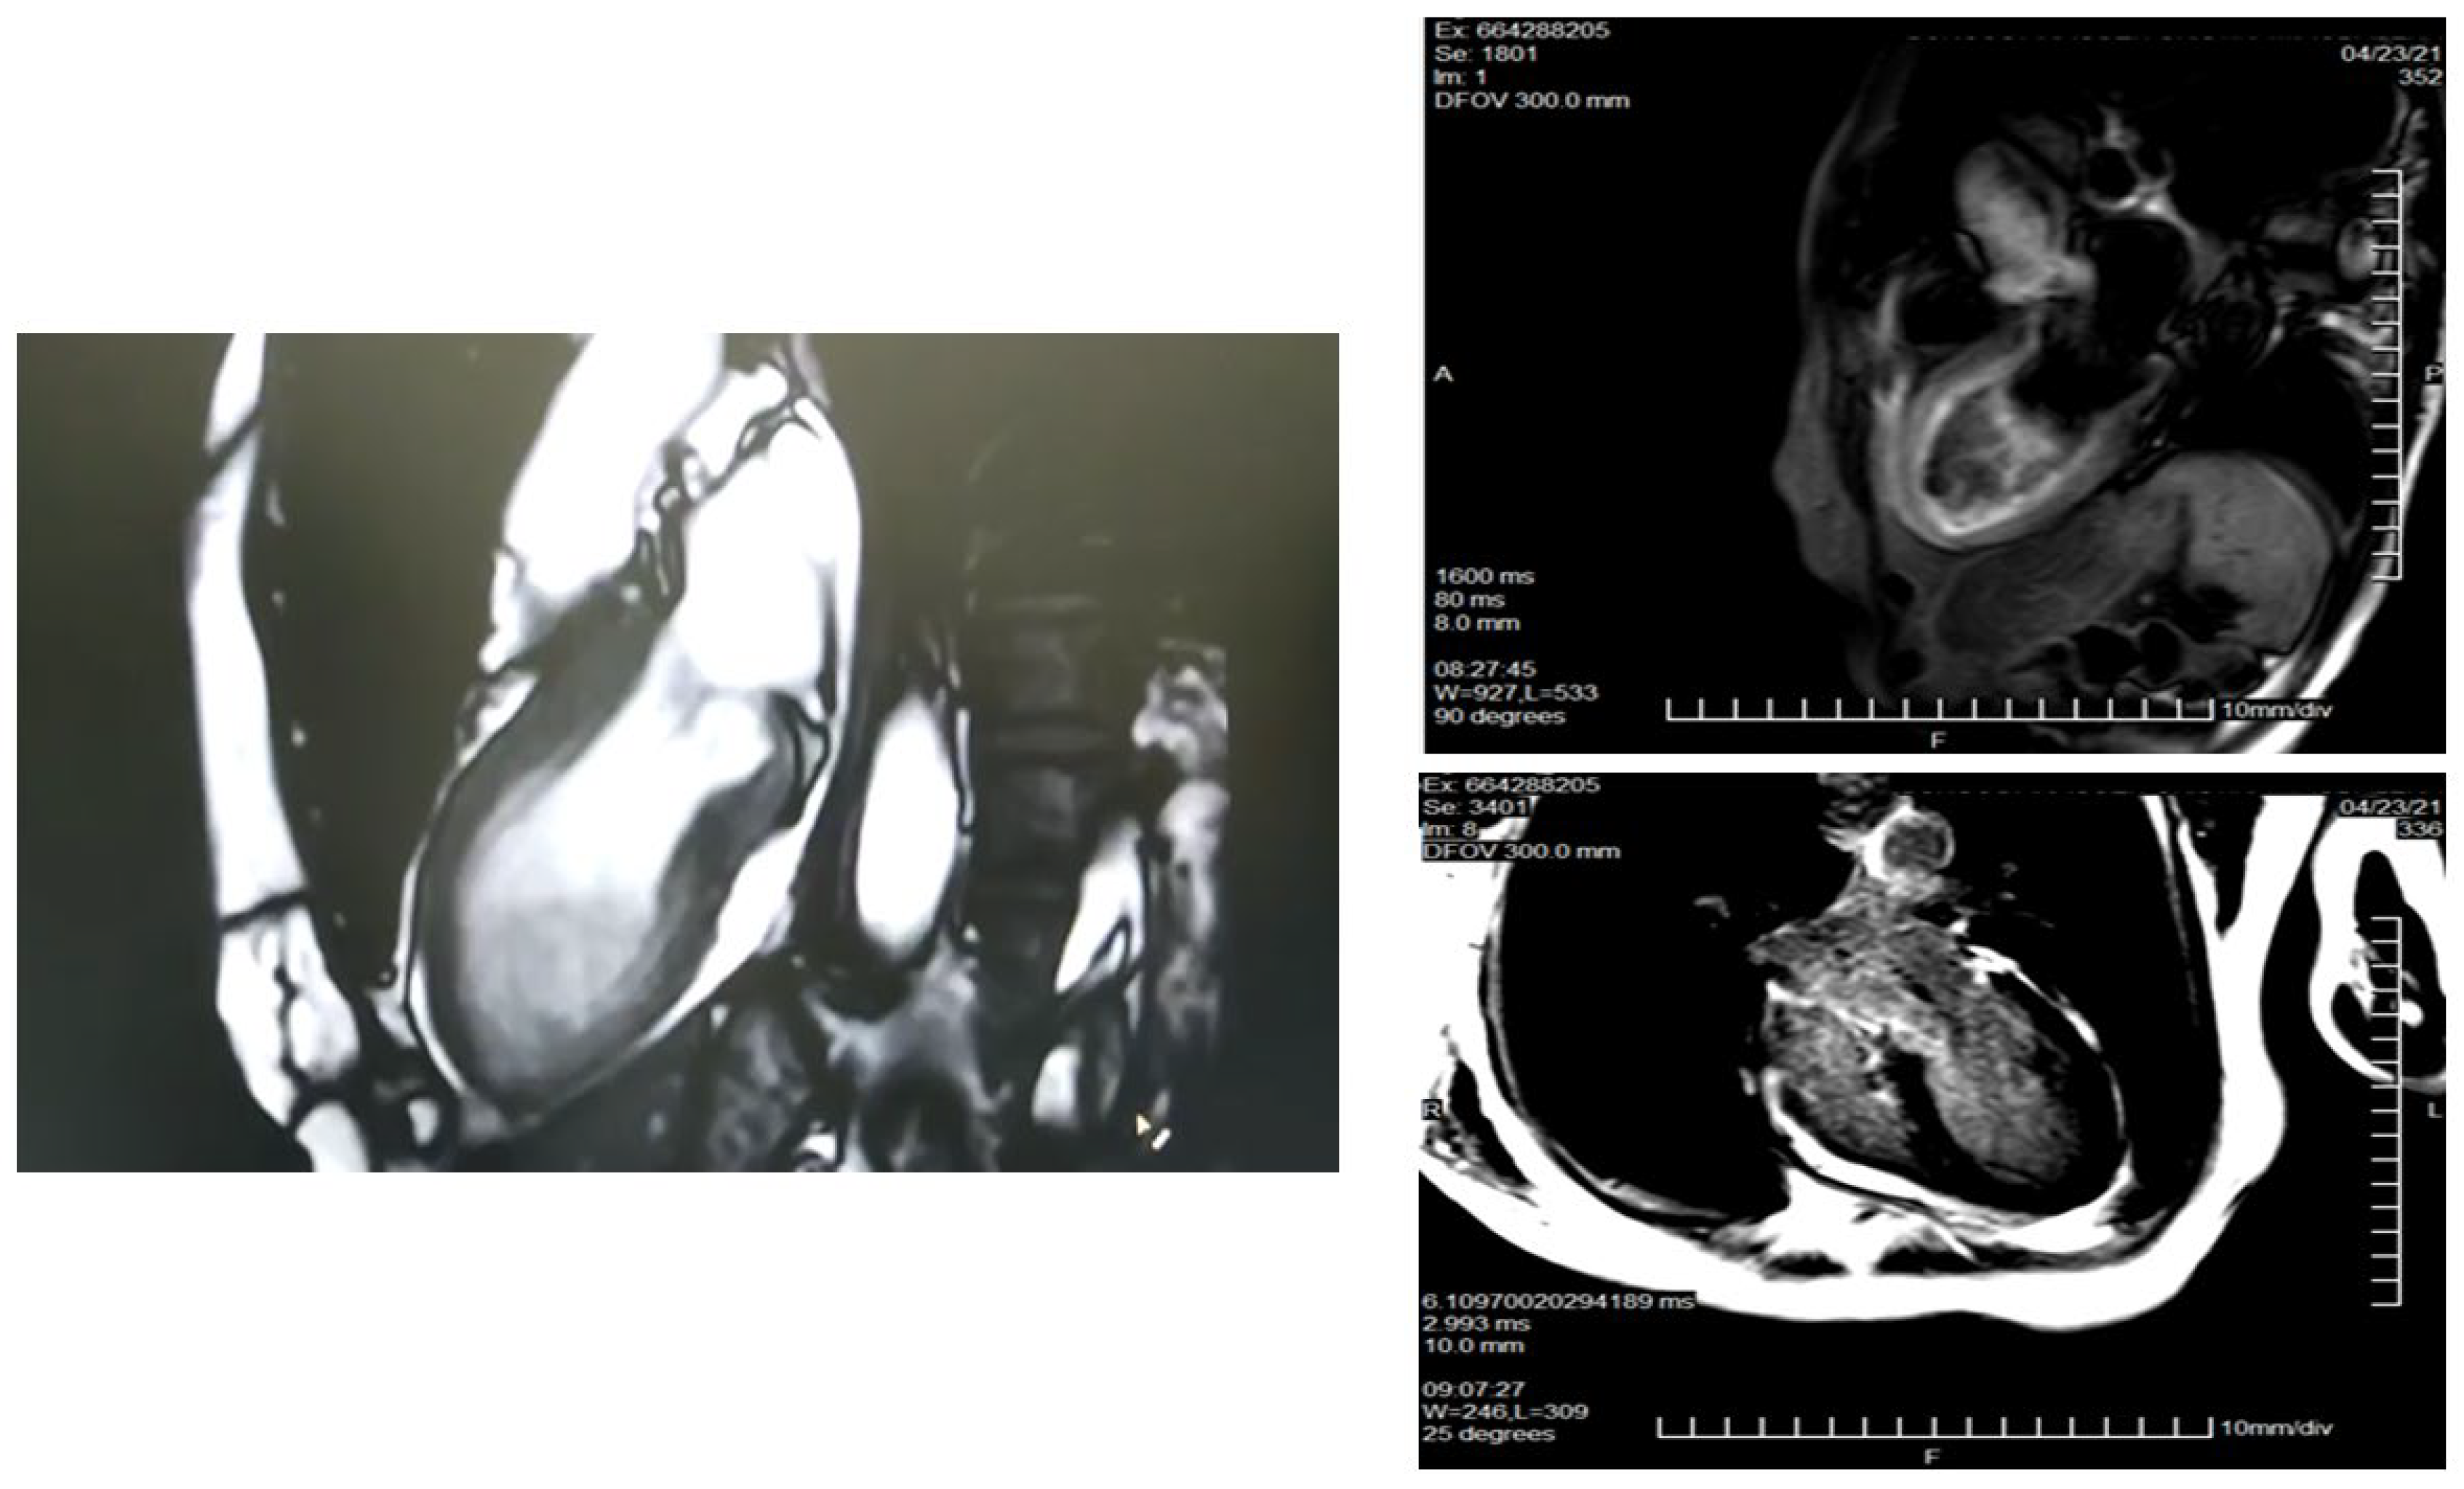

- Although the role of nuclear imaging in TTS has not yet been well established in clinical practice, assessments of myocardial perfusion, adrenergic innervation and metabolic activity may help in the diagnosis [88,89]. For instance, if there is normalized LV wall motion, the delayed recovery of glucose metabolism (by FDG-PET) and sympathetic innervation (by 123I-MIBG scintigraphy) may allow for the diagnosis of TTS in patients with delayed presentation. Although the coronary microcirculation is transiently compromised in TTS, its physiological role is still unclear. A reduction of perfusion tracer counts as a result of regional myocardial wall thinning at the apex, due to both artefacts and partial volume effects, which may mimic ACS, has been reported [86]. Figure 4 (SPECT-MPI) and Figure 5 (CMR) present the case of a patient with TTS.

Figure 4. SPECT MPI in a patient with Takotsubo syndrome. Female, 63 y.o., admitted for angina during the last hour. ECG: ST elevation V2-V6, troponin 761 ng/mL. Epicardial coronary arteries without lesions. SPECT-MPI: shows a perfusion defect in all the apical segments (rest study), with an intraventricular desynchrony by phase analysis (Phase SD: 73 degrees and histogram bandwidth 184 degrees), as well as wall abnormalities also in apical segments, with a LVEF slightly reduced (42%) at rest. ECG: electrocardiogram; SPECT: single photon emission tomography; MPI: myocardial perfusion imaging; SD: standard deviation; LVEF: left ventricular ejection fraction.

Figure 5. CMR in a patient with Takotsubo syndrome. Legend: Same patient as Figure 4. CMR study. Cine images with an apical ballooning. T2-weighted images showing myocardial oedema. There is no LGE. CMR: cardiac magnetic resonance; LGE: late gadolinium enhancement.